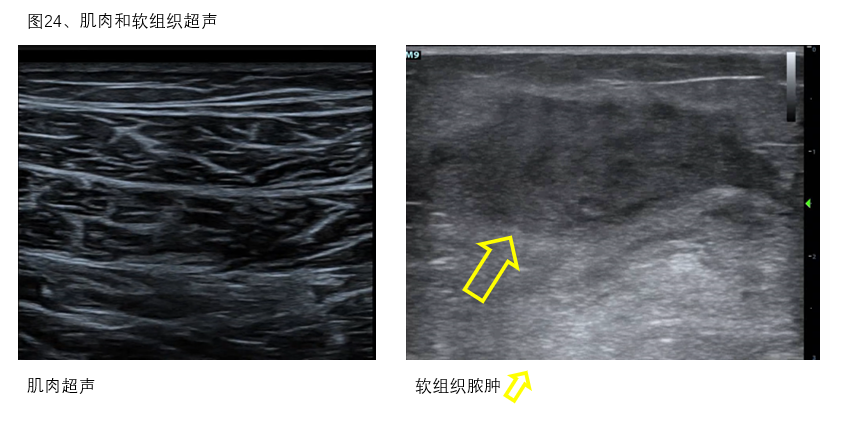

8、肌肉:在实施ECMO过程中对包括膈肌和骨骼肌在内的肌肉活动度和肌肉密度、厚度进行超声监测可以协助营养治疗和康复训练等[22](图24)。

图24